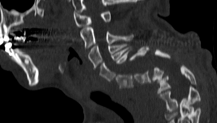

Kyphosis is the other major deformity disorder characterized by bending forward of the spinal column and can affect any region of the spine from the neck to the low back region. These can be caused by degenerative changes, previous surgery, and previous fracture/injury with healing in a bent-forward position.